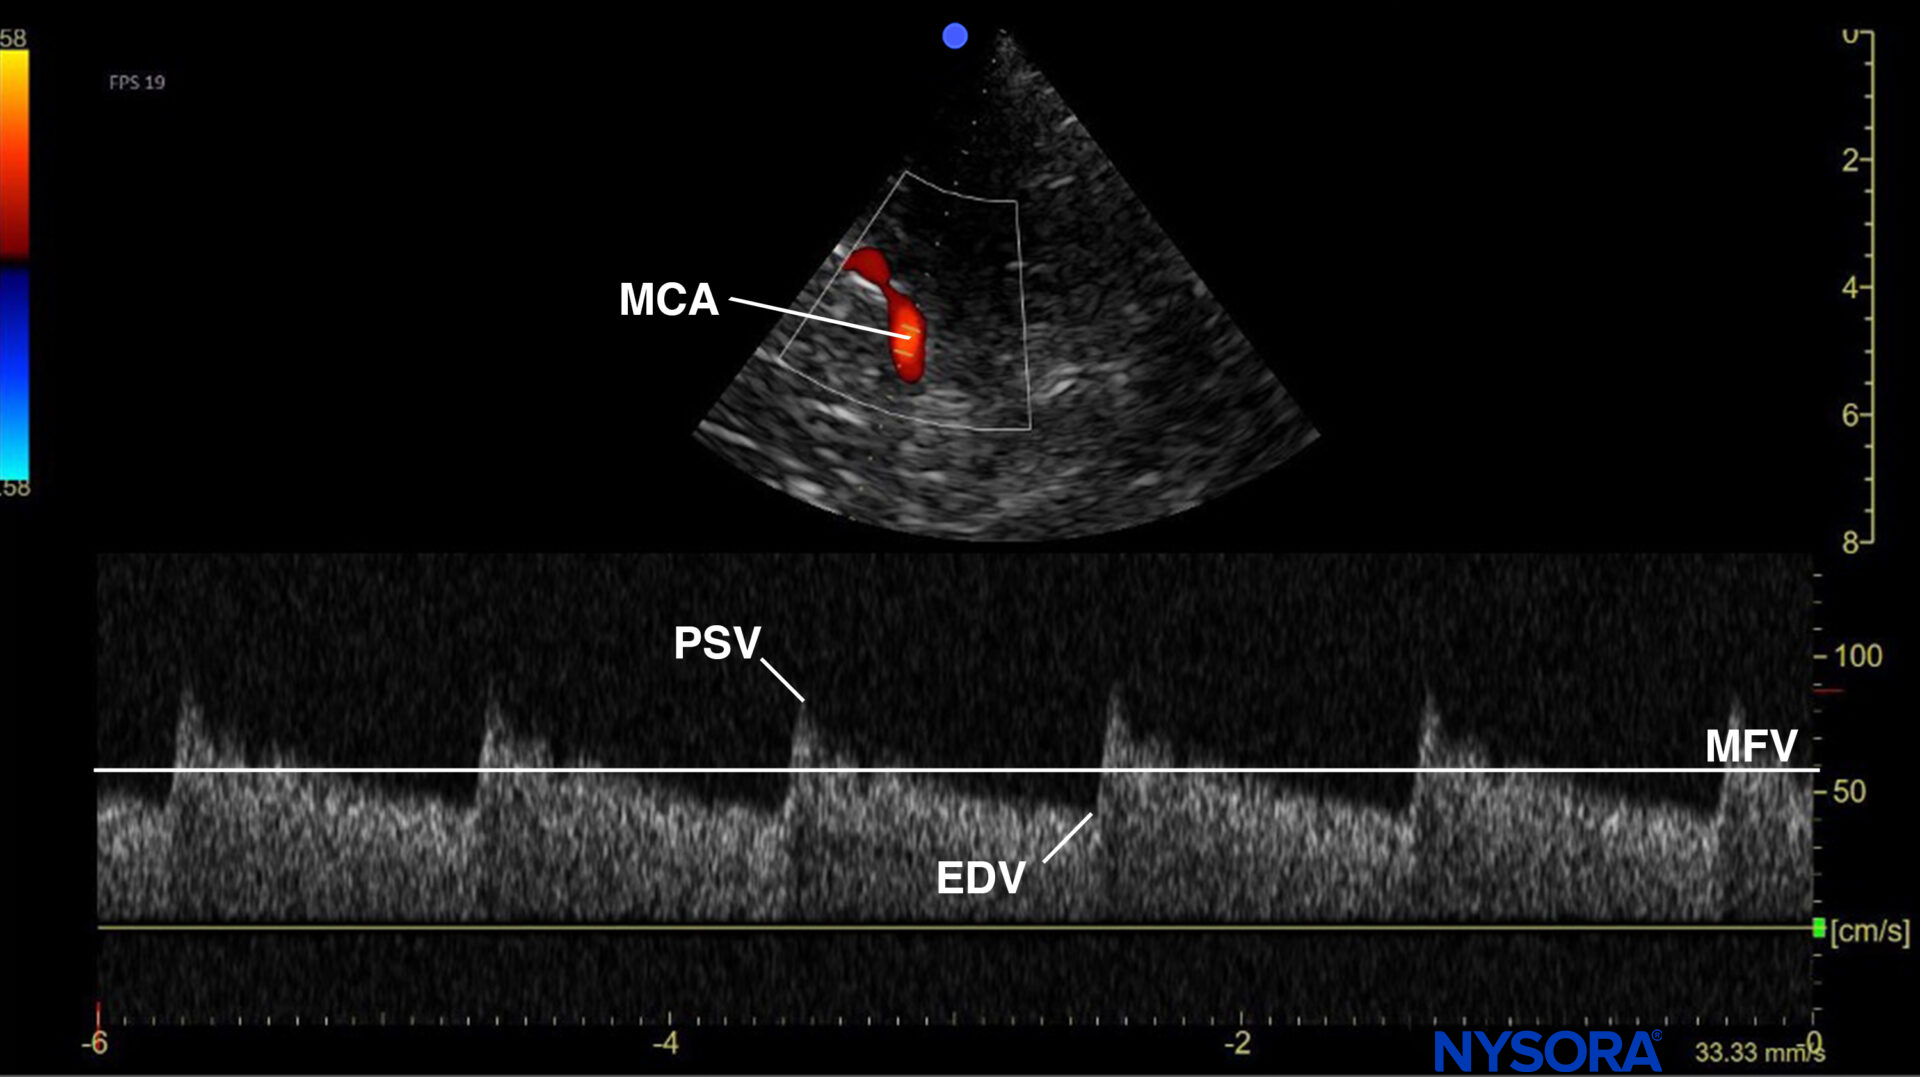

Use the mesencephalic plane and activate pulsed wave Doppler. Position the Doppler gate on the middle cerebral artery (MCA) and trace the flow velocities.

Mesencephalic plane pulsed wave Doppler with the Doppler gate on the middle cerebral artery (MCA). Evaluation of flow velocities in the MCA. PSV, peak systolic velocity; EDV, end-diastolic velocity; MFV, mean flow velocity.

In the presence of elevated intracranial pressure (ICP), different stages of diminished cerebral blood flow can be identified on MCA pulsed wave Doppler.

Six different phases can be identified in the process of cerebral circulatory arrest, but only the last three phases are considered compatible with cerebral circulatory arrest:

- The systolic and diastolic wave forms are preserved in the early phase.

- Blunting and loss of the diastolic waveform.

- Blood flow reversal during diastole due to high ICP.

- The area under the curve (AUC) during systole equals the AUC during diastole.

- Decrease in systolic flow with eventual no diastolic blood flow. These are also called systolic spikes and usually have flow velocities below 50 cm/s (and duration < 300 ms).

- Absence of cerebral blood flow.